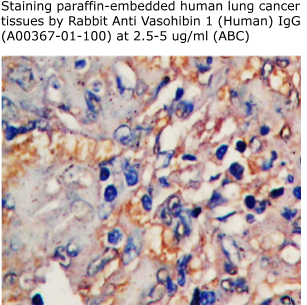

Primary Antibody: 100 ug of Rabbit anti Vasohibin1 (H) IgG

(A00367-01-100) at 2-4 ug/ml